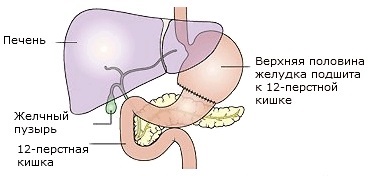

Diagrama arată anatomia stomacului dupa operatie Billroth I